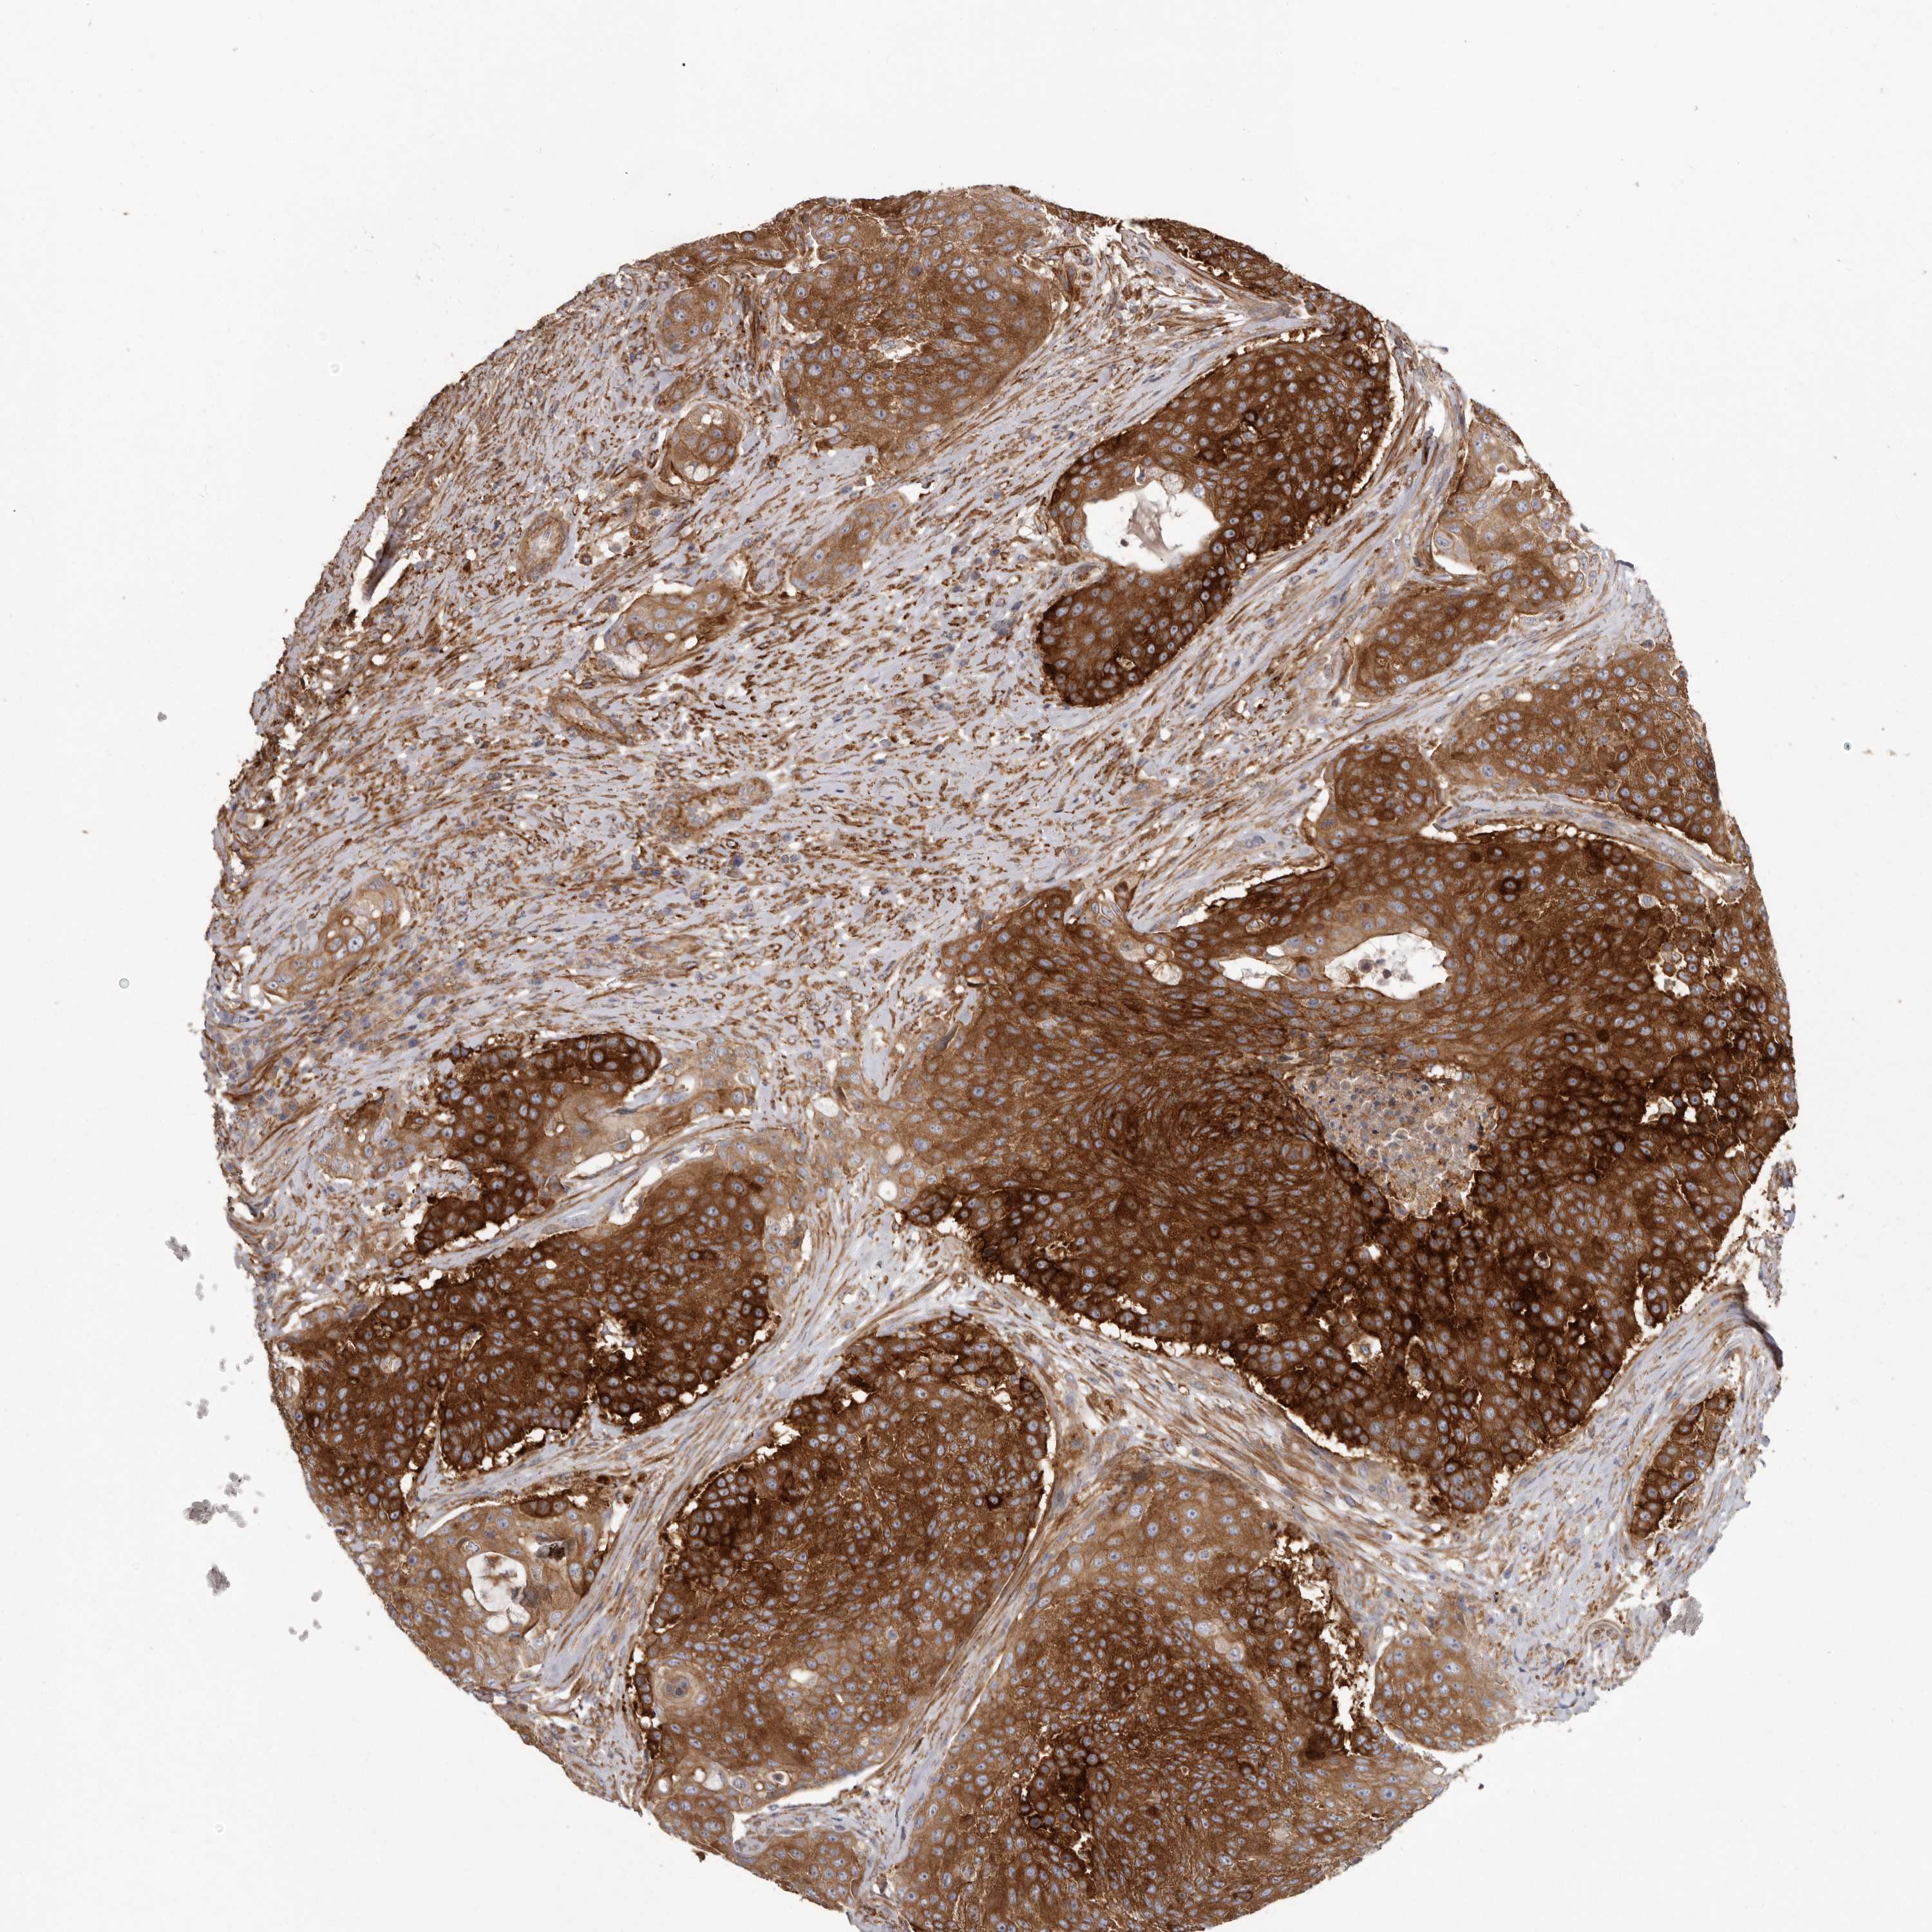

UROTHELIAL CANCER - Protein expressioni

A mouse-over function shows sample information and annotation data. Click on an image to view it in a full screen mode. Samples can be filtered based on level of antibody staining by selecting one or several of the following categories: high, medium, low and not detected. The assay and annotation is described here.

Note that samples used for immunohistochemistry by the Human Protein Atlas do not correspond to samples in the TCGA dataset.

Antibody stainingi

Antibody staining in the annotated cell types in the current human tissue is reported as not detected, low, medium, or high, based on conventional immunohistochemistry profiling in selected tissues. This score is based on the combination of the staining intensity and fraction of stained cells.

Each image is clickable and will lead to virtual microscopy that enables deeper exploration of all samples and also displays staining intensity scores, fraction scores and subcellular localization as well as patient and tissue information for each sample.

Antibody HPA028448

Antibody HPA028696

Urothelial carcinoma, Low grade

Urothelial carcinoma, High grade